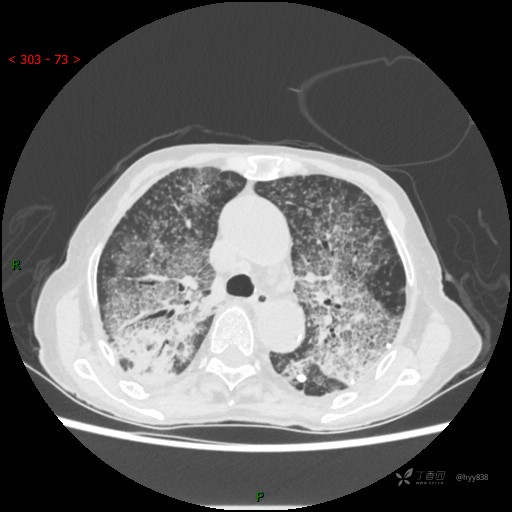

肺部弥漫性、疑难病变,感染或肿瘤?一元论或二元论?贴贴精彩---结果公布~

临床诊断:重症肺炎

胸部CT平扫